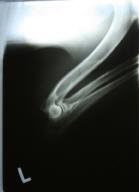

Allys Ellbogen gestreckt

ED: 0/0